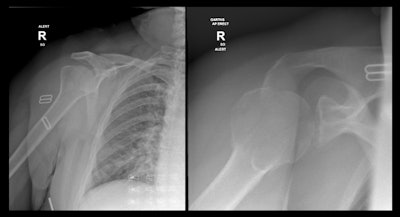

Greater tuberosity fracture overlooked on initial imaging.